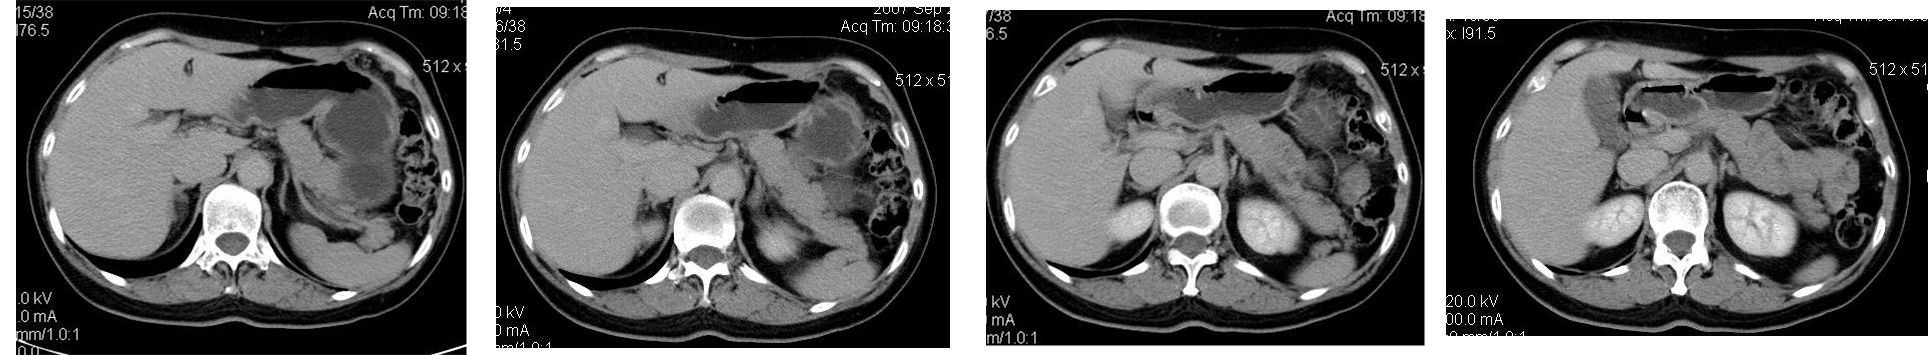

患者,女,65岁,住院准备甲状腺腺瘤用术,术前常规发现肝脏占位,ct增强扫描。

平扫

动脉期

门脉期

延迟扫描

符合快进快出表现,还是考虑:肝左叶内侧段肝癌.

造影剂快进快出,考虑:肝左叶内侧段肝癌.

肝左叶内侧段肝癌,肝右叶可见小结节灶,并见强化,考虑转移.

肝左叶内侧段低密度灶,增强明显快进快出表现,考虑:肝癌。

该患者去年9月份在我院ct检查,今年随访,患者家属介绍说上海中山医院做了一个什么检查考虑良性占位,后手术病理是血管平滑肌脂肪瘤。

学习了,这可能是脂肪含量少的血管平滑肌脂肪瘤,因血管丰富所以动脉期密度升高明显,但该患无肝硬化表现,所以,诊断肝癌,依据不足.谢谢上传.对今后工作是一个提醒.